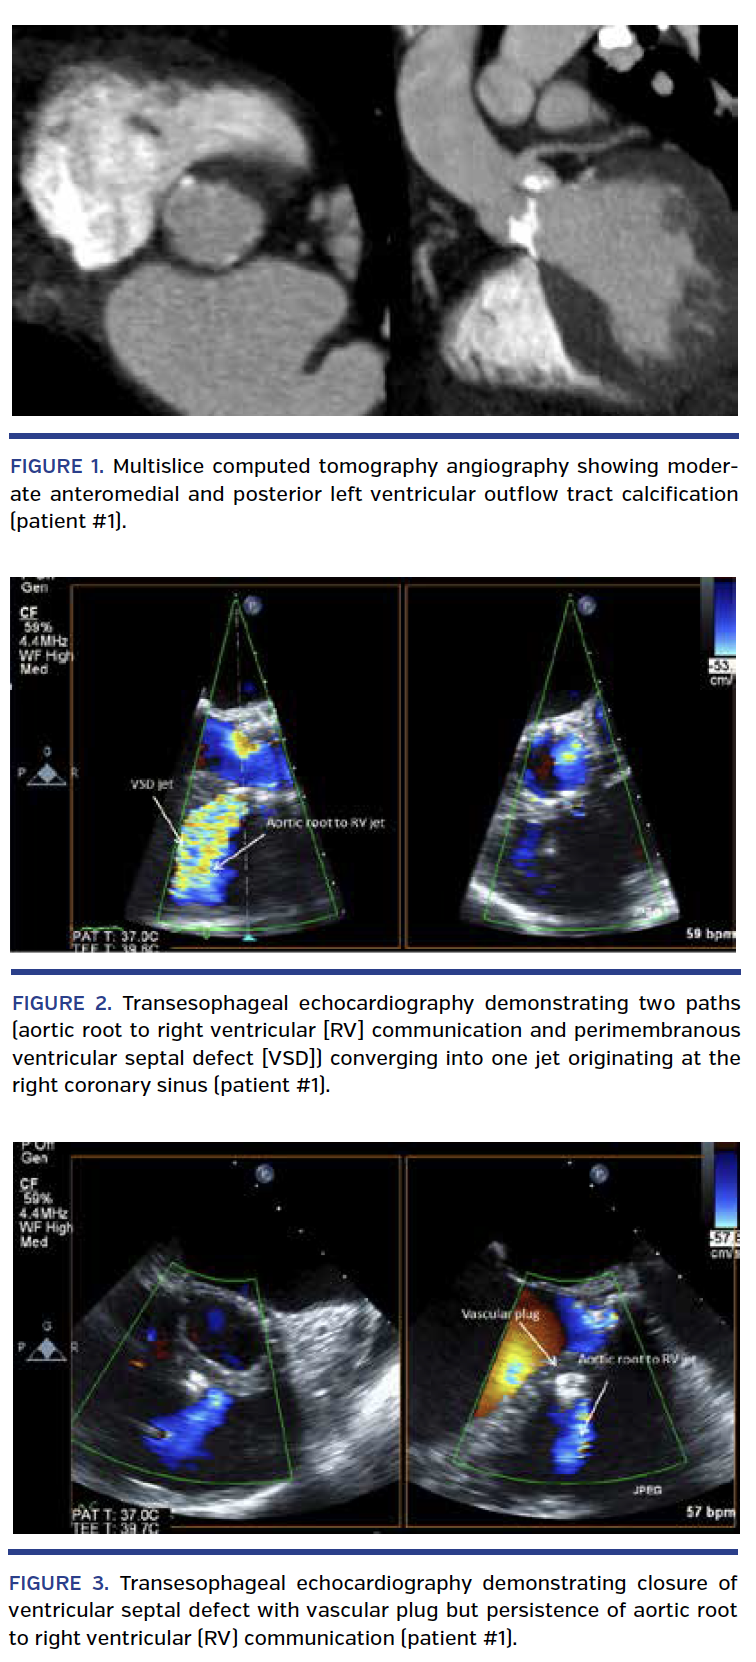

Patient #1. An 86-year-old woman with very severe AS presented to our institution with complaints of lightheadedness and reduction in exercise tolerance. Past medical history included hypertension, stage III chronic kidney disease, chronic obstructive pulmonary disease (COPD), and ankylosing spondylitis. Transthoracic echocardiogram (TTE) revealed left ventricular (LV) ejection fraction of 60% with peak and mean gradients across the aortic valve of 134 and 86 mm Hg, respectively. Aortic valve area (AVA) was calculated as 0.4 cm2. Cardiac catheterization revealed no evidence of obstructive coronary artery disease (CAD). Multislice computed tomography (MSCT) scan with angiography showed a heavily calcified mitral annulus, heavily calcified aortic valve, and atherosclerotic calcifications throughout the aorta and its distal branches, but otherwise patent femoral vessels. Aortic annulus minor and major diameters were 25 x 29 mm, with an area of 552 mm2. Area-derived diameter and perimeter were 26.9 and 85.2 mm, respectively. Oversizing by CT-derived aortic annular area was estimated at 19.7% (Table 1). Moderate anteromedial and posterior left ventricular outflow tract (LVOT) calcification can be seen in Figure 1. Although her STS score was calculated at 4.8%, given that she met three of four criteria for frailty,6 the heart valve team deemed her a more suitable candidate for TAVR.

The patient underwent successful deployment of a 29 mm Sapien XT valve (Edwards Lifesciences) prepared according to standard protocol via a transfemoral approach. Intraoperative transesophageal echocardiography (TEE) showed no paravalvular leak, but a small color Doppler jet from the LV to the right ventricle (RV) originating from below the aortic annulus, which was also confirmed on ventriculography. TTE performed 3 days postoperatively showed peak and mean gradient of 15 mm Hg and 7 mm Hg, respectively, across the prosthetic valve, an aortic root to RV communication, as well as a defect between the LVOT and the RV consistent with an iatrogenic VSD. No paravalvular aortic regurgitation (PAR) was detected. No new conduction abnormalities were noted on electrocardiogram (ECG). She was asymptomatic at the time of discharge.

The patient was initially managed conservatively, but she reported significant peripheral edema and persistent dyspnea on exertion at her 1-month follow-up visit. She underwent repeat TEE, which confirmed a moderate-sized fistula from the aortic root to the RV (larger defect) and a perimembranous VSD. Their two paths can be seen converging into one jet originating at the right coronary sinus (Figure 2; Video 1). Repeat cardiac catheterization confirmed left-to-right shunting from the aortic root and LVOT into the RV (Video 2). Pulmonary artery pressures increased from 31/6 mm Hg prior to the TAVR procedure to 65/27 mm Hg at follow-up. Qp/Qs was noted to be 2.3. Given her clinical decompensation and change in hemodynamics, it was decided that percutaneous closure of both defects would be attempted.

Closure of both defects was attempted under general anesthesia using TEE and angiographic guidance. VSD closure was performed using an 8 mm-diameter Amplatzer vascular plug 2 (St. Jude Medical) via an anterograde arteriovenous loop technique. An attempt to cross the aortic root to RV defect was unsuccessful, with persistence of significant shunting across the fistula (Figure 3; Video 3). She was seen 2 months after the partial closure and felt improved (New York Heart Association [NYHA] class II-III), but still had significant residual lower-extremity edema. Repeated TTE showed a residual gradient of 94 mm Hg across the aortic root to RV fistula. The patient died 4 months after her partial closure from complications associated with enterococcus bacteremia of an unclear source at a different institution. TEE performed prior to her death showed a well-functioning TAVR with mild PAR without evidence of vegetation.